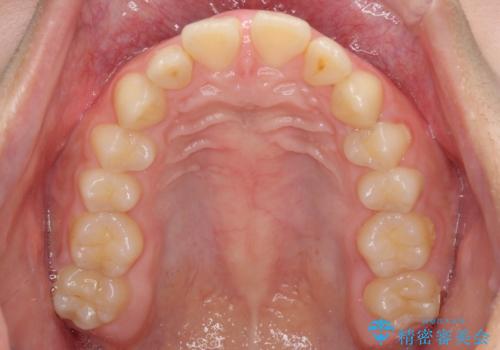

- 深い咬み合わせと上顎前歯の突出感を気にして来院された患者様です。

当院では通常、臼歯の咬合が理想的な位置に対して上顎が前方位にある場合。ワイヤー矯正または補助装置の併用したインビザライン矯正を選択しています。

今回は、できるところまででいいのでインビザライン単体で治療をしたいという希望があったため、インビザラインにて矯正治療を行うこととしました。

正面や横からの写真ではきれいに治っており、患者様は大変満足のいく仕上がりとなりましたが、深い咬み合わせの改善は不十分で、奥歯の咬み合わせも改善させることができませんでした。

インビザラインは、咬合力の強い方ですと、奥歯が歯肉内にめり込んでしまうため、前歯が強く接触してしまうことがあります。

こちらの方は、奥歯はしっかりと噛んだのですが、歯肉にめり込んでしまったことで、歯肉が腫れやすくなってしまいました。